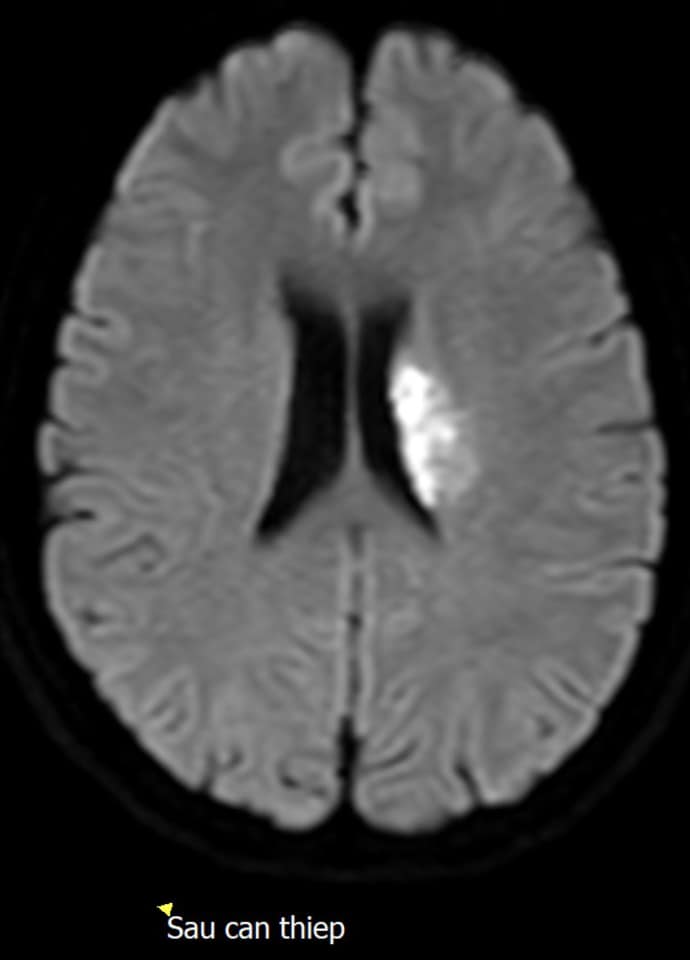

Trên phim cộng hưởng từ có tắc động mạch não giữa bên trái, vùng nguy cơ thiếu máu có thể cứu được có kích thước lớn hơn vùng hoại tử rất nhiều, nhóm đột quỵ đã hội chẩn nhanh chóng và quyết định hướng điều trị cho người bệnh là thực hiện can thiệp lấy huyết khối cơ học qua đường động mạch.

Trước khi can thiệp tay chân không thể tự nâng lên được, quá trình tái thông động mạch não giữa bị tắc trong thời gian 20 phút với 01 lần đưa dụng cụ lên lấy huyết khối, ngay sau khi kết thúc thủ thuật người bệnh phục hồi tay tự nâng lên và tự cử động đầu ngón và bàn chân.

Hiện tại người bệnh đi lại được và tỉnh táo hoàn toàn, được chuyển về khoa Nội - Hồi sức thần kinh để tiếp tục theo dõi và cho chụp cộng hưởng từ kiểm tra sau 24 giờ can thiệp, kết quả vùng nguy cơ thiếu máu sau tái thông có hình ảnh tưới máu như nhu mô não bình thường.